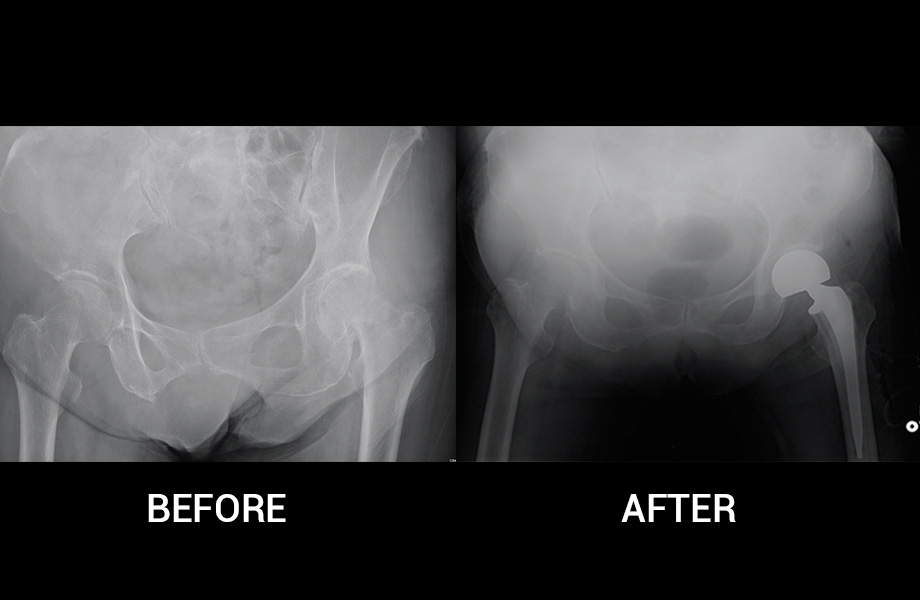

Hip Replacement